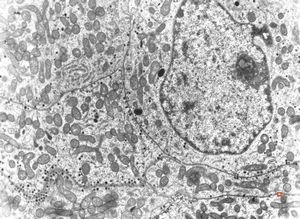

F, 72y. | carcinoid … metastasis to lymphonode